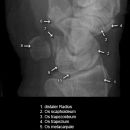

Handgelenk a.p.

Beurteilungskriterien

• Neigung der distalen Radiusgelenkfläche in der Frontalebene: 15 – 35°

• Längenverhältnis Radius – Ulna: Proc.styloideus radii überragt Gelenkfläche der Ulna um 9 –12mm (<9mm Ulna-Plusvariante, >12mm Ulnaminusvariante)

• Kontinuität der drei Karpalbögen:

Proximaler Bogen: proximale Gelenkflächenkonturen von Scaphoid, Lunatum und Triquetum

Mittlerer Bogen: distale Gelenkflächenkonturen von Sacphoid, Lunatum und Triquetum

Distaler Bogen: proximale Gelenkflächenkonturen von Capitatum und Hamatum

Fehlende Abgrenzbarkeit, Versatz oder Unterbrechung sind als pathologisch zu bewerten und deuten auf eine Luxation hin.

Trapezförmige Darstellung des Lunatum in Neutralstellung? Augenzeichen des Hamulus? Superposition von Pisiforme und Triquetum? Metacarpale III in Projektion innerhalb der Radiusgelenkfläche? Lunatum zu >50% über Radiusgelenkfläche? Cave: bei Radial- oder Ulnarduktion wandert das Lunatum in umgekehrter Richtung.

• M-förmiger Verlauf der Gelenkspalten der Carpometacarpalgelenke? Luxationsstellung in den Carpometacarpalgelenken (meist dorsale Luxation)?

• Gelenkspaltweiten des Radiocarpalgelenk 2 – 2,5mm, der Carpometacarpalgelenke 1 –2mm, distales Radioulnargelenk 2mm, Gelenksspaltweiten der Intercarpalgelenke 1,5 – 2mm

Cave: SL-Dissoziation (Ruptur des SL- Bandes, häufigste Gefügestörung): Terry-Thomas-Sign = SL-Spalt > 3mm, Siegelringzeichen = Ringförmige Transparenzminderung im mittleren Scaphoiddrittel durch orthograde Projektion der Taille infolge Rotation.

• Obliteration des Scaphoidfettstreifens?

• Täuschungsmöglichkeiten durch Vielzahl akzessorischer Ossikel (abgerundete, zirkulkär-geschlossene Kortikalis), geteilte Handwurzelknochen (Scaphoid, Lunatum, Pisiforme) und Gefäßkanälchen

• Target areas leicht zu übersehender Frakturen: distales Radioulnargelenk, Processus styloideus radii et ulnae, Basen der Metacarpalia (v.a. MCP I), Hamulus.

• Grundsätzlich gilt: unklare Verhältnisse ->CT-Indikation